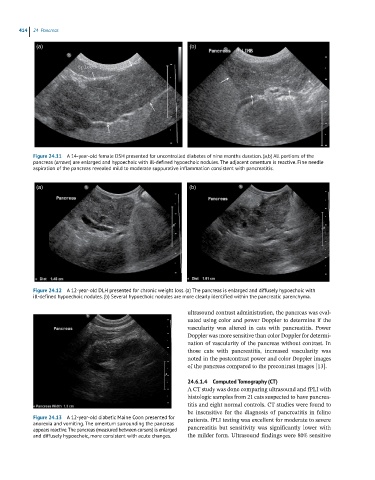

Figure 24.11 A 14-year-old female DSH presented for uncontrolled diabetes of nine months duration. (a,b) All portions of the

pancreas (arrows) are enlarged and hypoechoic with ill-defined hypoechoic nodules. The adjacent omentum is reactive. Fine needle

aspiration of the pancreas revealed mild to moderate suppurative inflammation consistent with pancreatitis.

Figure 24.12 A 12-year-old DLH presented for chronic weight loss. (a) The pancreas is enlarged and diffusely hypoechoic with

ill-defined hypoechoic nodules. (b) Several hypoechoic nodules are more clearly identified within the pancreatic parenchyma.

Figure 24.13 A 12-year-old diabetic Maine Coon presented for patients. fPLI testing was excellent for moderate to severe

anorexia and vomiting. The omentum surrounding the pancreas

appears reactive. The pancreas (measured between cursors) is enlarged pancreatitis but sensitivity was significantly lower with

and diffusely hypoechoic, more consistent with acute changes. the milder form. Ultrasound findings were 80% sensitive